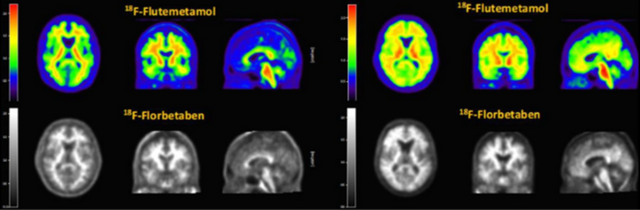

듀켐바이오가 독점 공급계약을 따낸 GE헬스케어의 비자밀과 바이엘의 뉴라체크는 다양한 글로벌 치매 신약 임상시험에서 환자 선정 및 치료 효과 판단에 사용되고 있다. 이 두 제품의 진단용 동위원소인 F-18은 반감기가 110분으로 제조 후 2시간이면 약효가 절반으로 감소한다. 이 때문에 비자밀, 뉴라체크 공급을 위한 계약 과정에서 듀켐바이오가 가진 전국 의약품 제조·품질관리기준(GMP) 생산시설과 물류 시스템이 높은 점수를 받았다.

그는 “우리가 뉴라체크, 비자밀 두 가지 진단제를 제조하고 있는데 병원이 뉴라체크를 쓰다가 비자밀로 바꾸는 경우, 비자밀을 쓰다가 뉴라체크로 바꾸는 경우는 거의 없었다”며 “제품마다 이미지 차이가 작지만 분명히 존재하므로 갑자기 다른 진단제로 바꿀 경우 기존 환자의 이미지는 더 이상 환자 상태를 비교하는 용도로 쓸 수 없게 되기 때문”이라고 말했다.